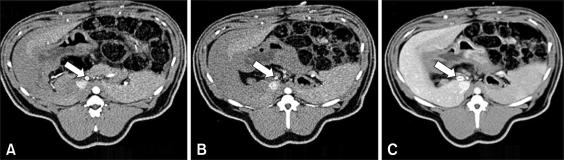

The shortage of organ donors has stimulated interest in the possibility of using animal organs for transplantation into humans. In addition, pigs are now considered to be the most likely source animals for human xenotransplantation because of their advantages over non-human primates. However, the appropriate standard values for estimations of the liver of micropigs have not been established. The determination of standard values for the micropig liver using multi-detector row computed tomography (MDCT) would help to select a suitable donor for an individual patient, determine the condition of the liver of the micropigs and help predict patient prognosis. Therefore, we determined the standard values for the livers of micropigs using MDCT. The liver parenchyma showed homogenous enhancement and had no space-occupying lesions. The total and right lobe volumes of the liver were 698.57 +/- 47.81 ml and 420.14 +/- 26.70 ml, which are 51.74% and 49.35% of the human liver volume, respectively. In micropigs, the percentage of liver volume to body weight was approximately 2.05%. The diameters of the common hepatic artery and proper hepatic artery were 6.24 +/- 0.20 mm and 4.68 +/- 0.13 mm, respectively. The hepatic vascular system of the micropigs was similar to that of humans, except for the variation in the length of the proper hepatic artery. In addition, the diameter of the portal vein was 11.27 +/- 0.38 mm. In conclusion, imaging evaluation using the MDCT was a reliable method for liver evaluation and its vascular anatomy for xenotransplantation using micropigs.